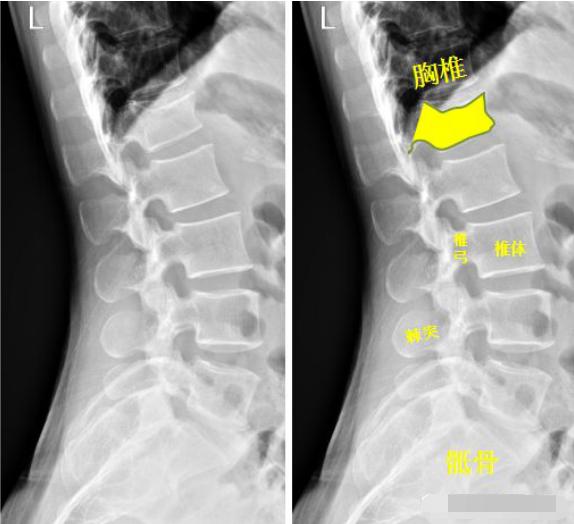

患者洗澡摔倒,腰部着地,拍片如下:

腰椎侧位示:第1腰椎呈前低后高楔形改变,腰椎第1椎体陈旧性压缩性骨折。